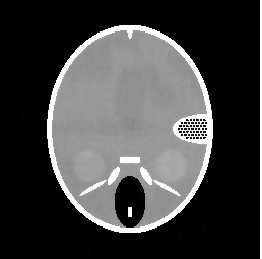

In this section we report the results of several tests run on simulated under-sampled data obtained by synthetic (phantoms) and full resolution MRI images. The under-sampled data are obtained as where is the full resolution image and is the under-sampling Fourier matrix, obtained as in (5). The under-sampling masks, analyzed in the next paragraphs are: radial mask (), parallel mask () and random mask (). In figure 1 we represent an example of each mask with low sampling rate , measured by the percentage ratio between the number of non-zero pixels and the total number of pixels :

| (48) |

In this paragraph we test the performance of FNCR algorithm in reconstructing good quality images from highly under-sampled data. We focus on two synthetic images: the Shepp-Logan phantom (T1) (figure 2(a)), widely used in algorithm testing, and the Forbild phantom (T2) [21] (figure 2(b)), well known as a very difficult test problem.

Concerning the real MRI data we compare IL and FNCR algorithms in the reconstructions of the brain image (T3 test), represented in figure 8. We report in table 6 the results obtained by reconstructing the noiseless data undersampled by , , masks.